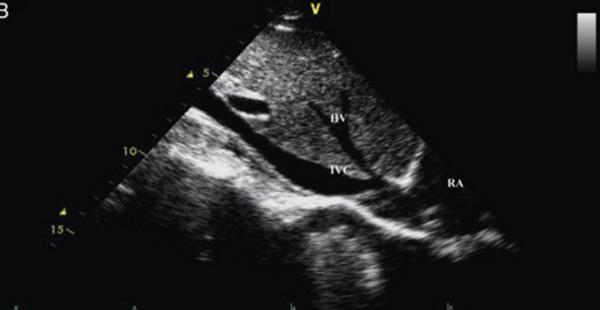

Budd-Chiari

Life threatening emergency

Portal vein Thrombosis - cavernous transformation

replacement of the normal single channel portal vein with numerous tortuous venous channels.